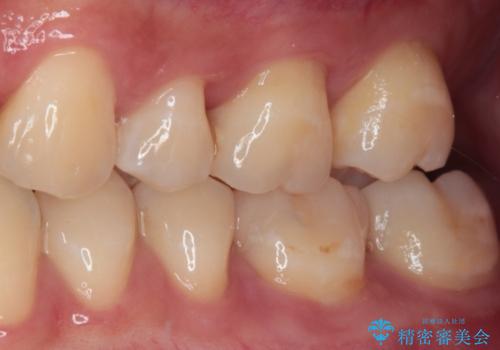

奥歯がしみる 保険の詰め物をセラミックインレーに

- 奥歯が食事の度にしみてしまうとのことで来院された患者様です。

目視やレントゲン写真からは、以前処置された部分に大きな問題は認められませんでしたが、冷たい風をかけると強い痛みを感じる状態でした。

患者様と相談の上、詰め物を全て外した上でむし歯があるかどうかを確認し、セラミックインレーで精密な修復治療を行うこととしました。

精密な型取りと、ラバーダム防湿下での接着操作により、歯と詰め物の隙間を最小限にとどめることができ、処置後はしみる症状が一切なくなりました。